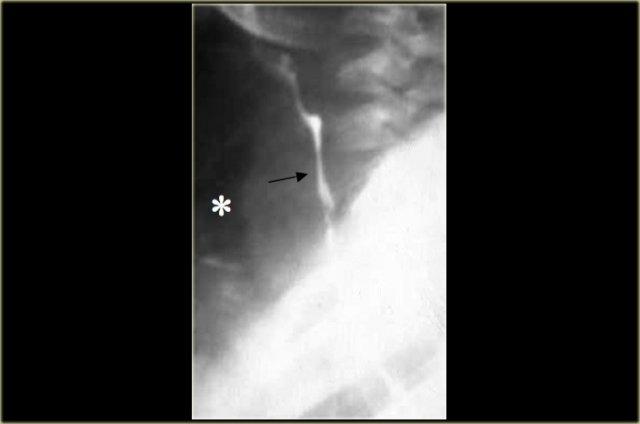

Hình ảnh này thuộc về một bệnh nhân mắc hội chứng Boerhaave.

X-quang ngực cho thấy tràn khí trung thất (các mũi tên).

Chụp thực quản cản quang cho thấy thuốc cản quang tan trong nước thoát ra ngoài lòng mạch ở nửa ngực trái (dấu hoa thị).

Thủng hầu như luôn xảy ra ở phía trái của thực quản đoạn xa.